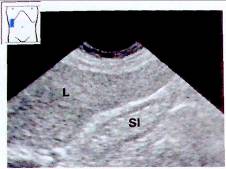

Рис.14. Эхогенный желчный пузырь. Желчный пузырь полностью заполнен эхогенным сладжем (S1). Дистальная акустическая тень отсутствует. L — печень.